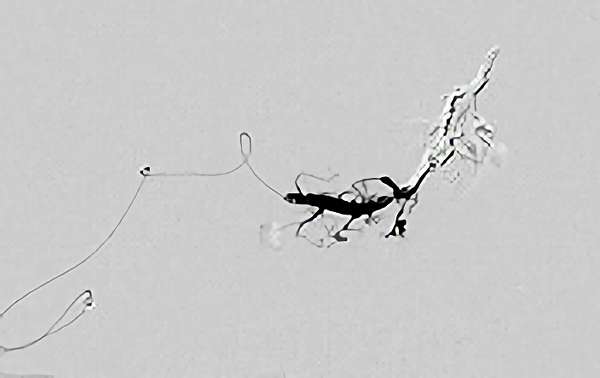

No.1620 手術中